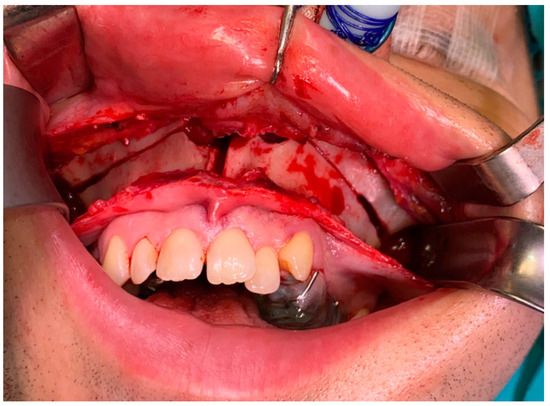

- Type 2 in-pure SSS (iSSS) (Figure 3, Figure 4 and Figure 6) related to maxillary deformation (might be related to maxilla-mandibular skeletal class II/III deformities or others), clinically asymptomatic, not related to trauma or surgery, 1–3 MS walls retracted, OMC clear, no opacification, like suggested by Lee et al., the “not so silent sinus” [18];